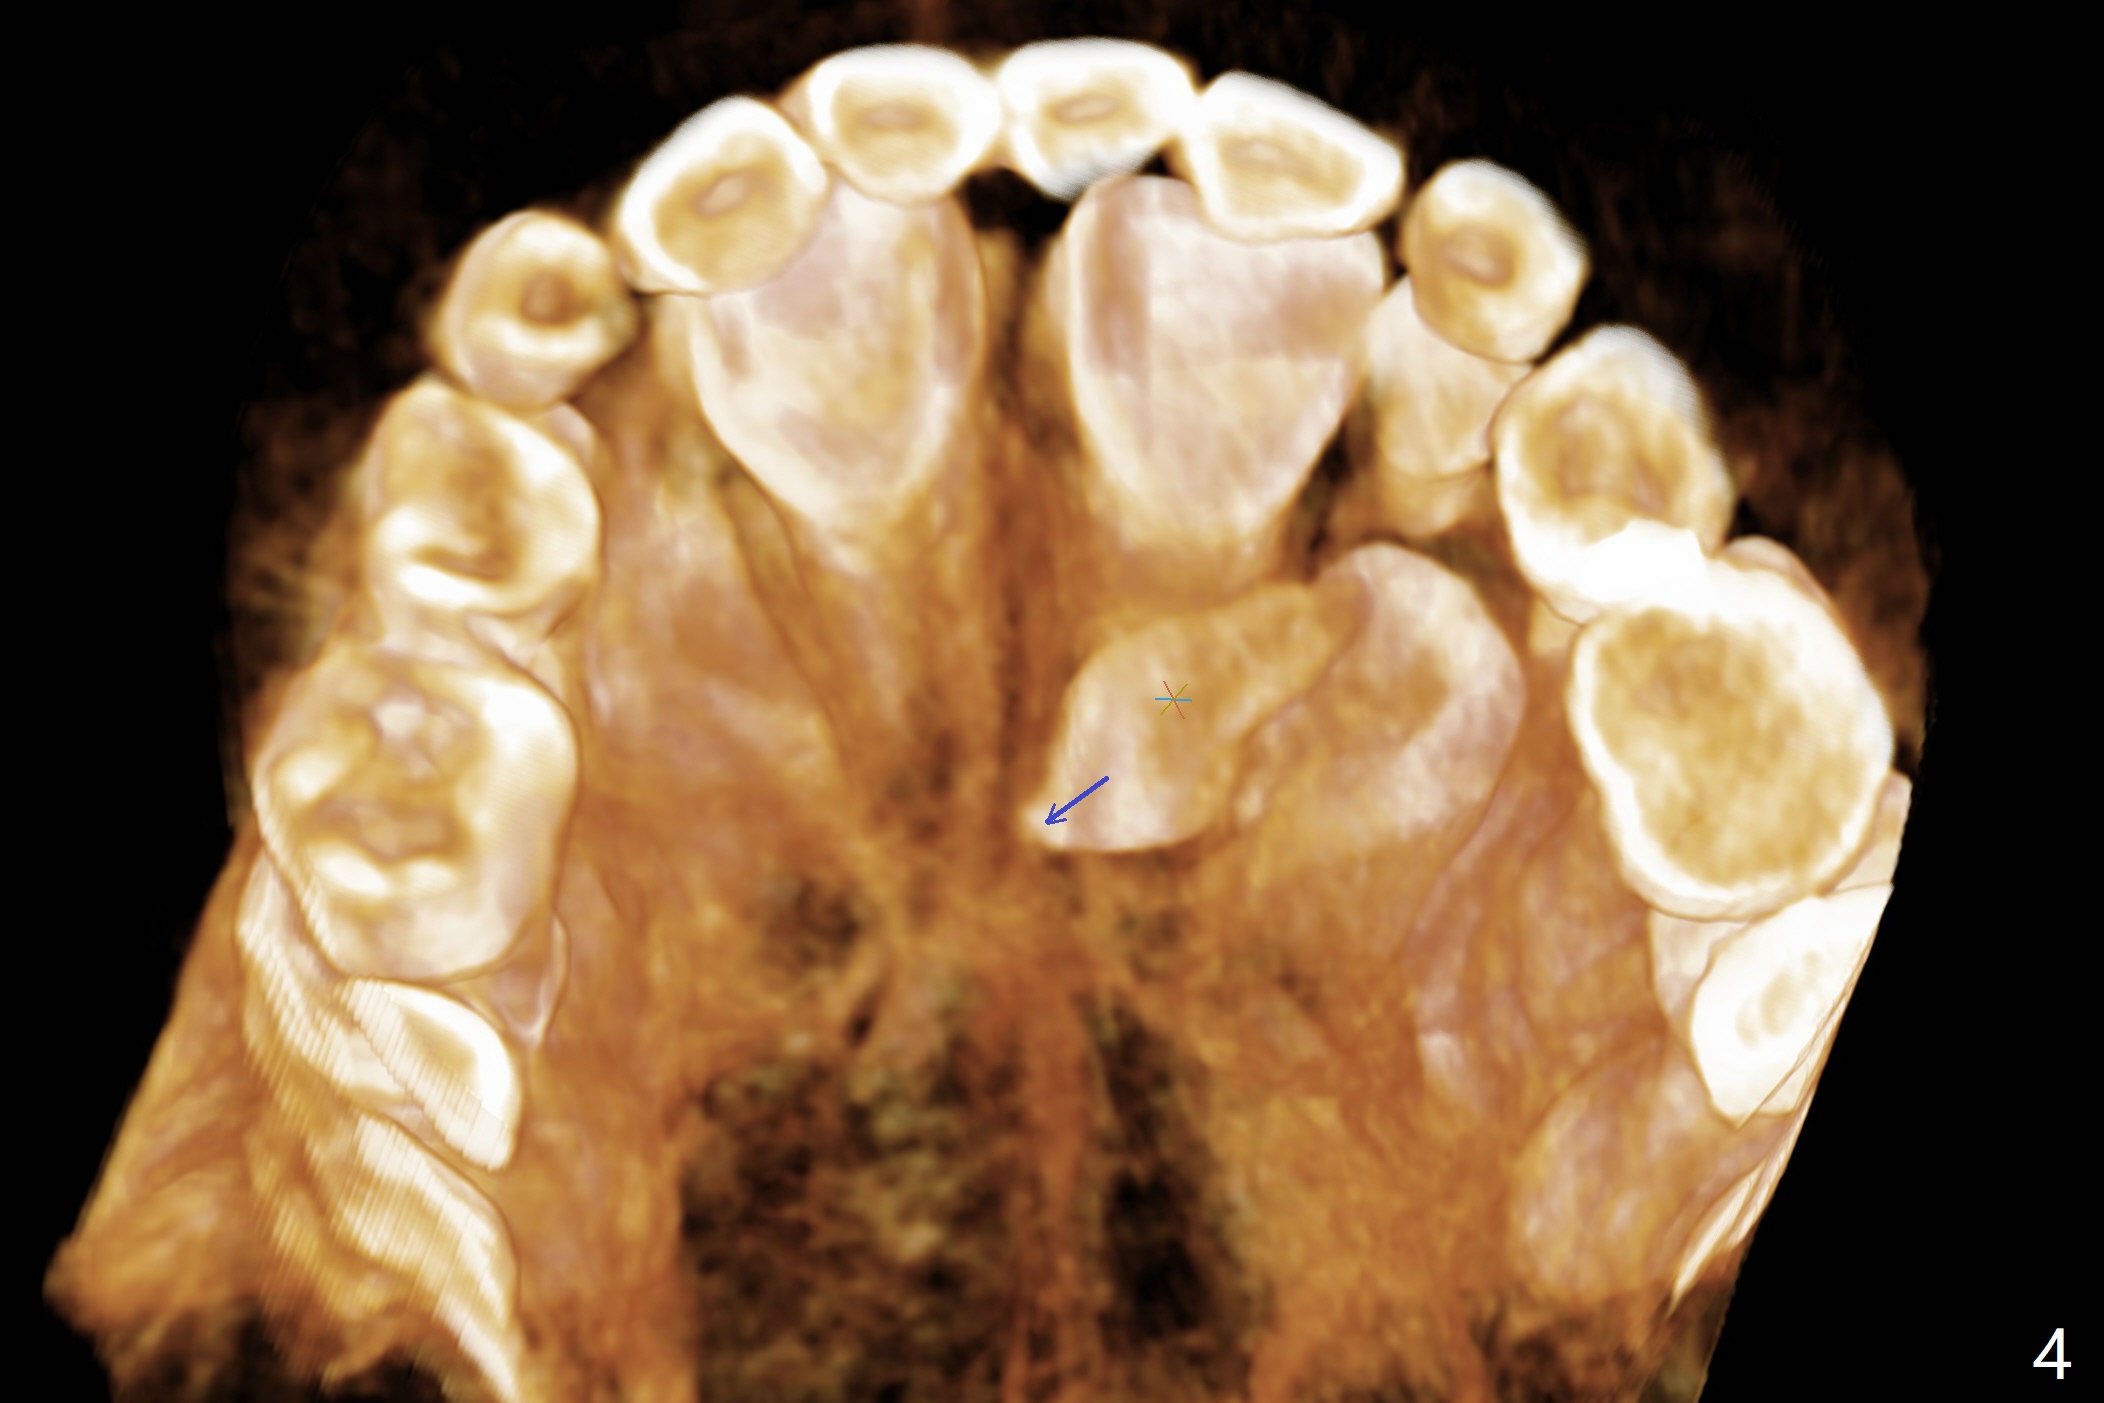

The father of a 7-year-old boy wonders why the upper central incisors, particularly #9, are off (Fig.1 3-D CT tooth coloring). Fig.2 (bone coloring) does not reveal much. Fig.3 (MIP, more transparent) reveals a supernumerary tooth, called mesiodens (M, an extra central incisor, abnormally shaped (cone), near the midline). Palatal view shows that the mesiodens points to the midline and distal (arrow). A palatal gingival sulcus incision will be made to expose the extra tooth (Fig.5). An elevator will be used as midline and distal as possible to avoid damage to the root of #9 and the tooth bud of #10 (Fig.6 MIP). Photos will be taken frontally and palatally preop and after incision and exposure of the mesiodens (palatal).